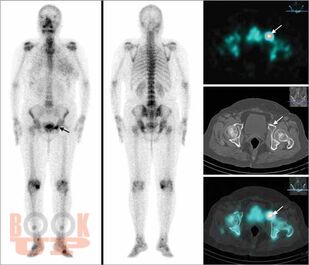

All chapters have been thoroughly revised. The present edition has incorporated 4 new chapters in the musculoskeletal subsections and 2 new chapters in the breast subsection. Content has been divided into 7 different subsections, beginning with current concepts and interventions. The first section deals with all imaging modalities in musculoskeletal imaging. There is an updated section on MR imaging, including new additions of imaging of wrist and ankle; peripheral nerve imaging and imaging of prosthetic joints. The second part of the book contains updated chapters on Breast imaging and interventions and includes two new chapters on Male Breast Imaging and Advances in Breast Imaging. This edition will serve as a concise yet comprehensive guide for students and practitioners of radiodiagnosis as well as a ready reckoner to clinicians in understanding the basics as well as current advances in imaging and interventions.